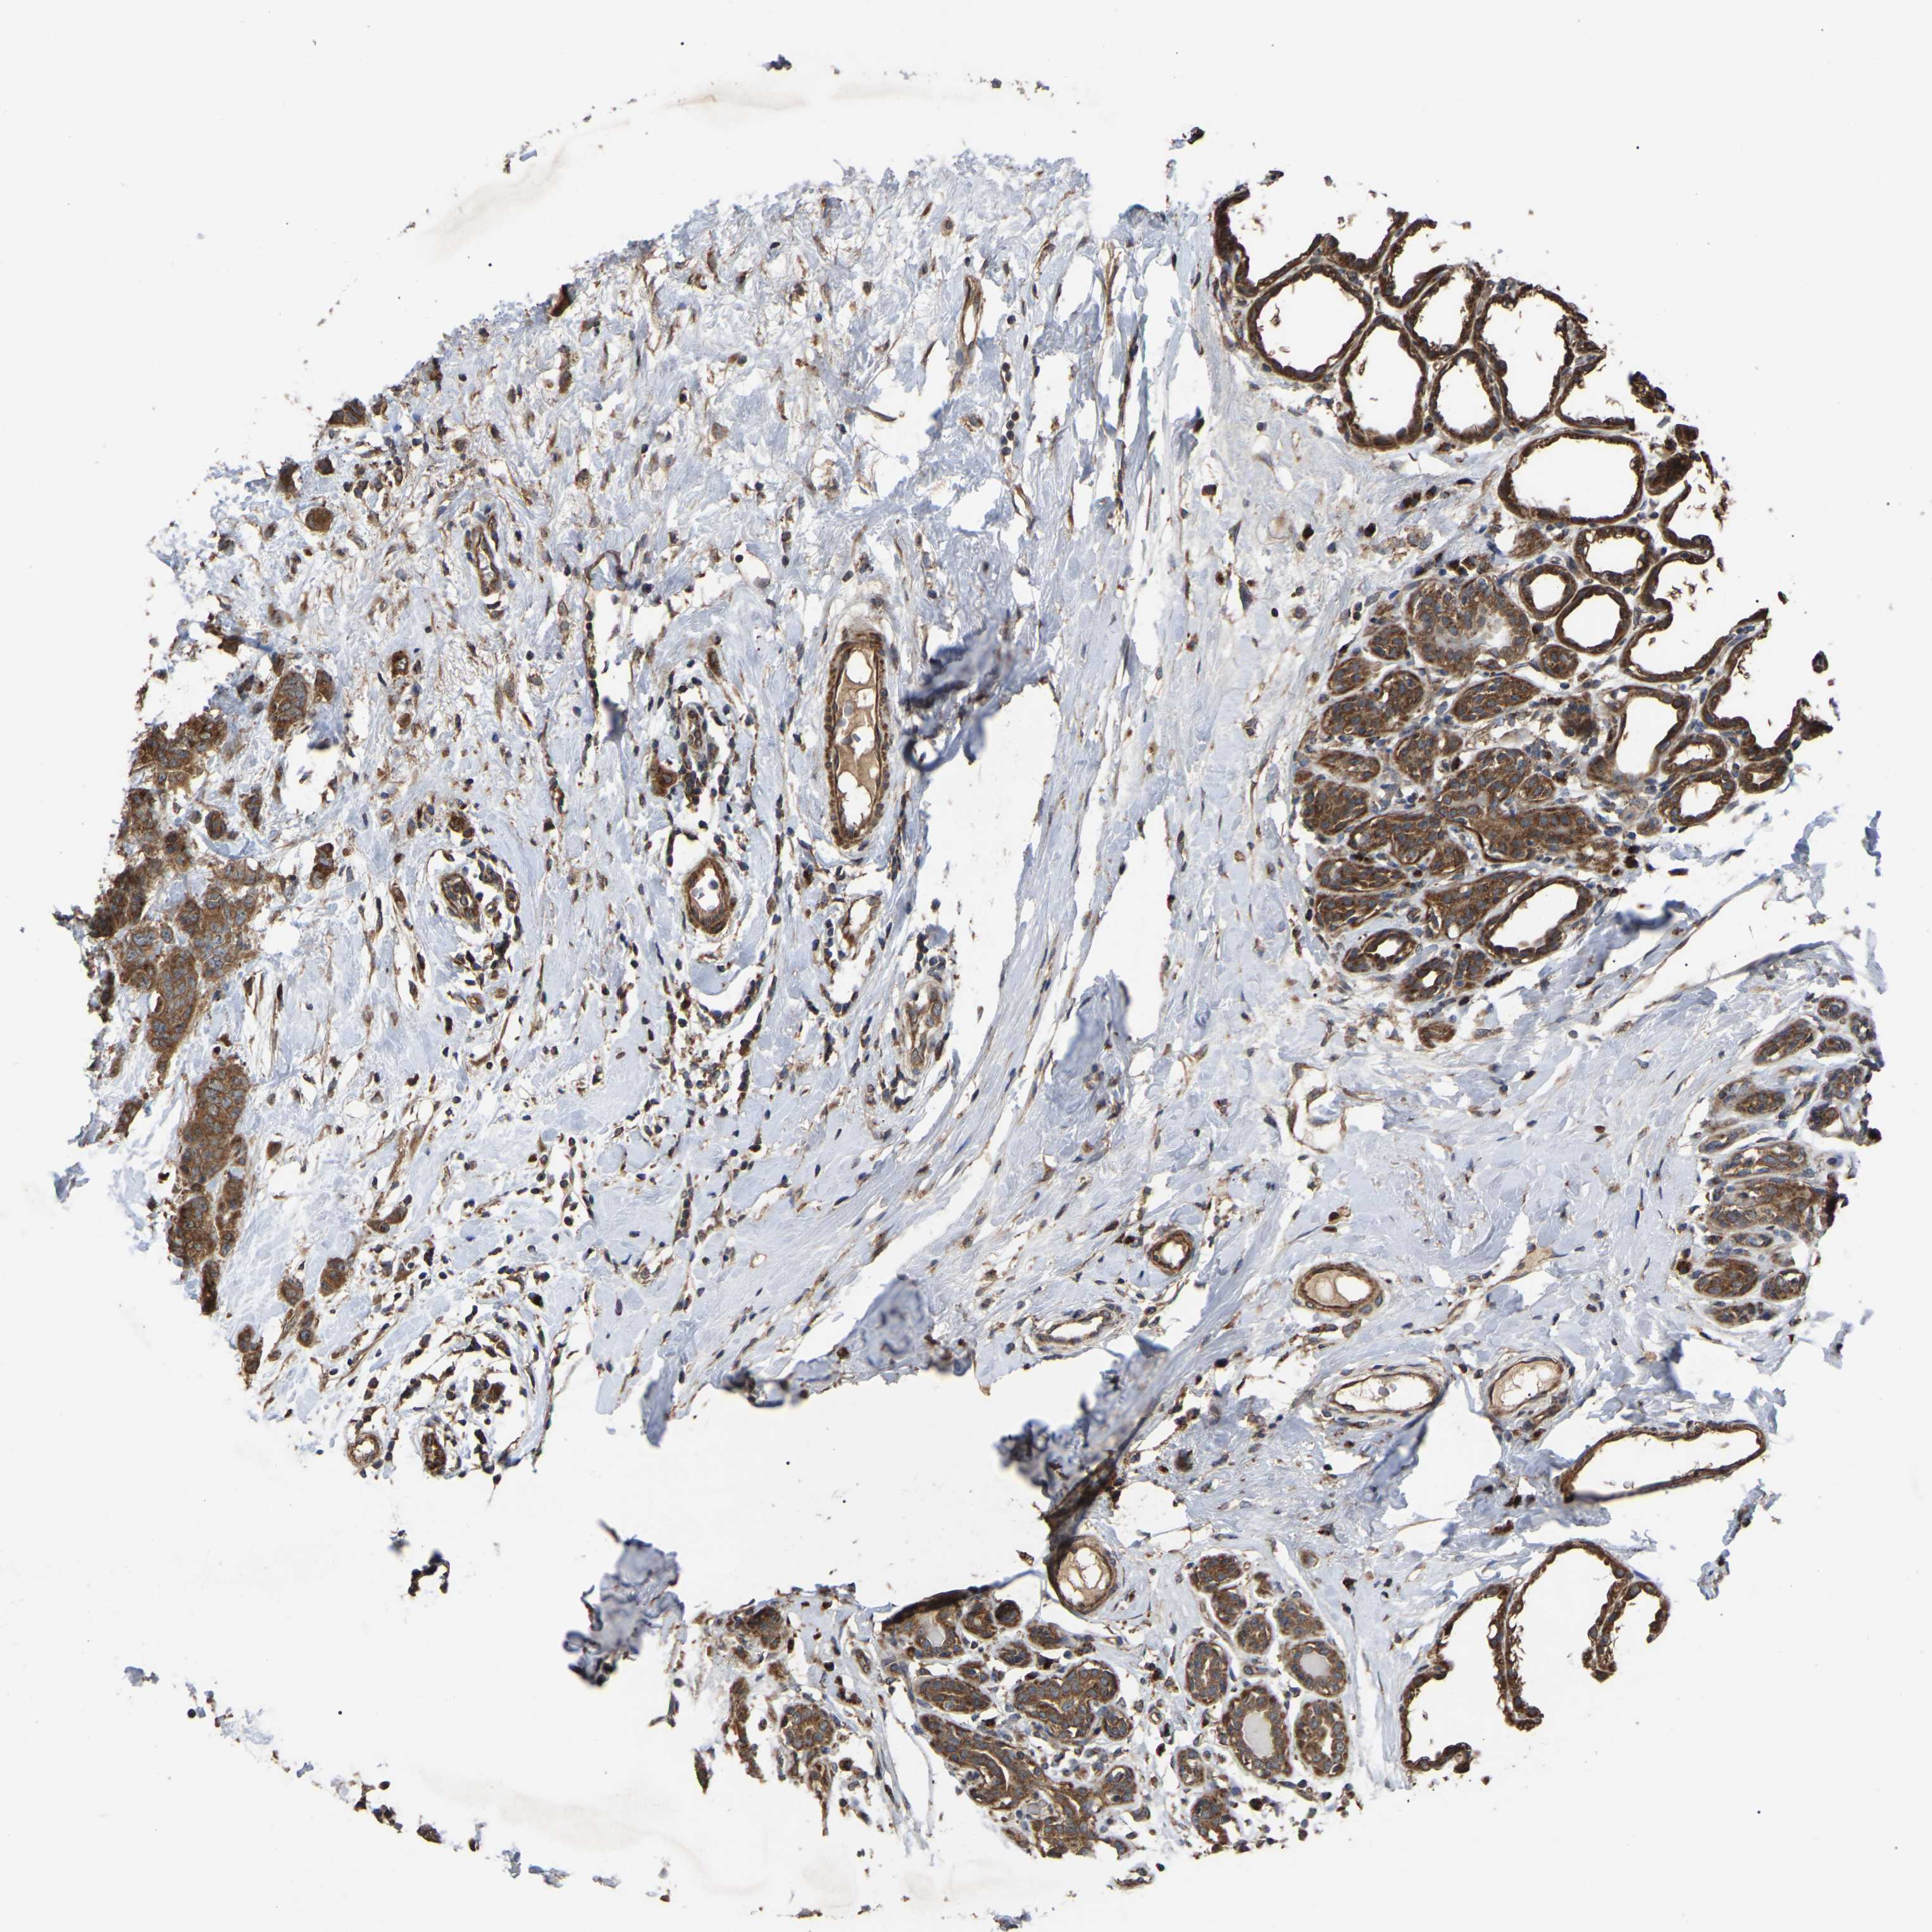

CANCER BREAST CANCER Show tissue menu

BRCA TCGA BRCA VALIDATION PROTEIN EXPRESSION

ANTIBODIES

AND

VALIDATION